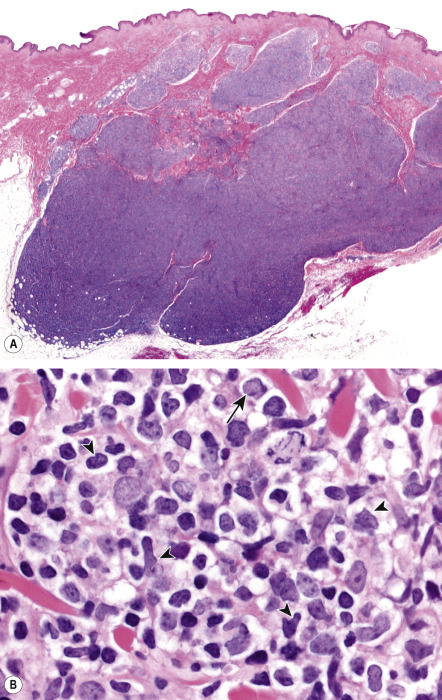

In PCFCL, nodular or diffuse infiltrates are seen within the entire dermis, often extending into the subcutaneous fat ( Fig. 119.6A ) . The epidermis is usually spared. A clear-cut follicular pattern with formation of neoplastic germinal centers was observed in only a minority of cases (25%) in the series from Graz ( Fig. 119.7 ) . However, a higher percentage of cases may show at least some follicular architecture. In those with a follicular pattern, the neoplastic follicles show morphologic features of malignancy, including the presence of a reduced or absent mantle zone, the lack of tingible body macrophages, and a monomorphism of the follicles – so-called “dark” and “clear” areas are no longer recognizable (see Fig. 119.7 [inset]) .

In both the follicular and diffuse variants, centrocytes (small to large, cleaved follicle center cells) predominate within the neoplastic infiltrate ( Fig. 119.6B ) and are admixed with a variable number of centroblasts (large, non-cleaved follicle center cells with prominent nucleoli), immunoblasts, small lymphocytes, histiocytes, and, in some cases, eosinophils and plasma cells. In contrast to nodal FCLs, grading is not used for the classification of PCFCL . On a cytomorphologic basis, some cases of PCFCL with a diffuse pattern of growth and a predominance of large centrocytes have the appearance of a large cell lymphoma, but the prognosis of these cases is similar to that of lesions without the large cell morphology . Patients with a monotonous proliferation of centroblasts and/or immunoblasts should be classified as having diffuse large B-cell lymphoma. An accompanying infiltrate of small T lymphocytes and histiocytes/macrophages is usually present, and, in some instances, these cells can be predominant.